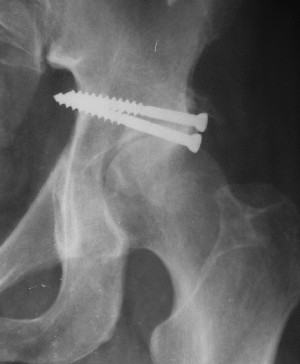

Послеоперационный снимок прямой 5/05/03

|

Больной 18 мая 2003 года в автоаварии получил перелом левой вертлужной впадины, вывих бедра. Госпитализирован в один из стационаров области.Вывих вправлен. В последствии бедро вывихивалось еще дважды. На консультацию был представлен снимок от 19.05.03г., больной переведен к нам 3.06.03г. Снимок при поступлении - перелом впадины, задне-верхний вывих бедра. 05.06.2003 г. выполнено открытое вправление вывиха левого бедра и остеосинтез стенки вертлужной впадины двумя винтами. Послеоперационный период без осложнений. Объем движений в левом тазобедренном суставе восстановился полностью. Выписан на амбулаторное лечение в удовлетворительном состоянии с рекомендациями 3 месяца ходить на костылях без нагрузки на оперированную конечность. На контрольных рентгенограммах левого тазобедренного сустава 13.10.2003 г. - признаки консолидации перелома; плотность, форма головки и состояние суставных поверхностей удовлетворительные. Разрешена дозированная осевая нагрузка, на конечность с использованием дополнительной опоры. 19.12.2003 г. больной обратился с жалобами на боли в левом тазобедренном суставе. На рентгенограммах левого тазобедренного сустава 19.12.2003 г., 20.02.04г. - асептичекий некроз головки бедра. 5.04.04г. - эндопротез. Сейчас ходит без трости, не хромает. Особенность эндопротезирования - при удалении винтов прослежена линия перелома заднего края впадины и предложено установить чашку несколько меньшего диаметра, чтобы она была покрыта несломанной частью.